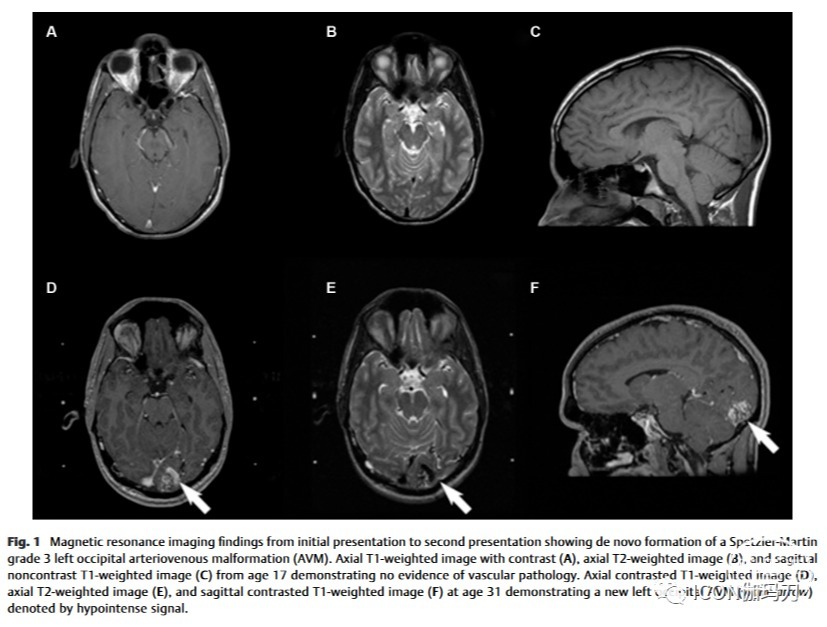

一个17岁的男性,有AVM的家族史(包括一个兄弟有胼胝体AVM),因偏头痛伴有视觉先兆和全身性癫痫发作而就诊于急诊室。患者接受了高分辨率磁共振成像(MRI)检查,未发现任何颅内病理(图1A-C)。患者持续出现罕见的反复发作,但由于患者和父母的偏好,在任何时候都没有开始使用抗癫痫药物。患者既往有静脉用药史、丙型肝炎感染史、糖尿病前期史。

图1磁共振成像结果从最初的表现到第二次表现显示重新形成的Spetzler-Martin 3级左枕动静脉畸形(AVM)。17岁的轴位T1加权图像(A),轴位T2加权图像(B)和矢状面平扫的T1加权图像(C)显示没有血管病变的证据。31岁时,轴向T1加权对比像(D)、轴向T2加权像(E)和矢状面T1加权对比像(F)显示新的左枕部AVM(白色箭头),以低信号显示。

在初次就诊14年后,这位31岁的患者因癫痫发作时头部受伤而向急诊科报告。头部CT血管造影显示左侧枕叶内1.9 × 1.4 cm高衰减血管团块(图2),无出血迹象。脑血管造影证实存在未破裂的2.9 cm的 Spetzler-Martin 3级左枕部AVM(图3)。AVM由大脑后动脉的胼胝体支和颞后支供血,并有浅静脉引流和深静脉引流。该枕部AVM在当时的MR成像上也得到了证实(图1D-F)。